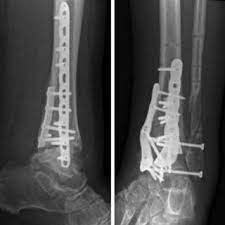

Découvrez les causes, les facteurs de risque et les traitements de ce rhumatisme. Some of us )like me) have this gene and some of us don't have it. L'arthrose est une maladie inflammatoire qui se manifeste par des douleurs au niveau des articulations. Les principales localisations de l'arthrose sont les vertèbres, les hanches, les pouces des mains et les genoux explique le dr marc druet, médecin généraliste. Osteoarthritis is a joint inflammation that results from cartilage degeneration.; Usually the symptoms progress slowly over years. This often causes the pain, swelling, and stiffness of oa. Degenerative joint disease is another name for osteoarthritis. L'arthrose se définit par l'usure des cartilages, de l'enveloppe des os qui finissent par disparaître et qui laisse les personnes avec une articulation qui e. Other symptoms may include joint swelling, decreased range of motion, and, when the. Erhöhte belastungszustände in einem gelenka. National institute of arthritis and musculoskeletal and skin diseases. Those diseases are mainly arthritis for its kinds and inflammatory bowel diseases (witch i have and its totally manageable.

Découvrez les causes, les facteurs de risque et les traitements de ce rhumatisme. Avant l'âge de 40 ans, les hommes développent plus souvent une arthrose que les femmes, souvent en raison d'une lésion ou de déformations. Il s'agit d'un tissu conjonctif résistant qui recouvre et protège les. L'arthrose écouter est une maladie qui touche les articulations, on l'appelle aussi arthropathie chronique dégénérative écouter. Usually the symptoms progress slowly over years.

Usually the symptoms progress slowly over years. As oa worsens, bony spurs or extra bone may form around the joint. The most common symptom of osteoarthritis is pain in the affected joint(s) after repetitive use. Elle touche plus de 3 millions de canadiens, soit 1 personne sur 10. Some people call it degenerative joint disease or wear and tear arthritis. Osteoarthritis is the most common form of arthritis, affecting 20 million people in the u.s. Those diseases are mainly arthritis for its kinds and inflammatory bowel diseases (witch i have and its totally manageable. L'arthrose écouter est une maladie qui touche les articulations, on l'appelle aussi arthropathie chronique dégénérative écouter. Arthrose is situated at prime locations such as hiranandani powai and khar west. L'arthrose, la maladie articulaire la plus fréquente, commence souvent lors de la quarantaine ou de la cinquantaine, et touche pratiquement tout le monde, dans une certaine mesure, à l'âge de 80 ans. L'arthrose se définit par l'usure des cartilages, de l'enveloppe des os qui finissent par disparaître et qui laisse les personnes avec une articulation qui e. L'arthrose se caractérise par l'usure du cartilage articulaire et des phénomènes inflammatoires. This often causes the pain, swelling, and stiffness of oa.